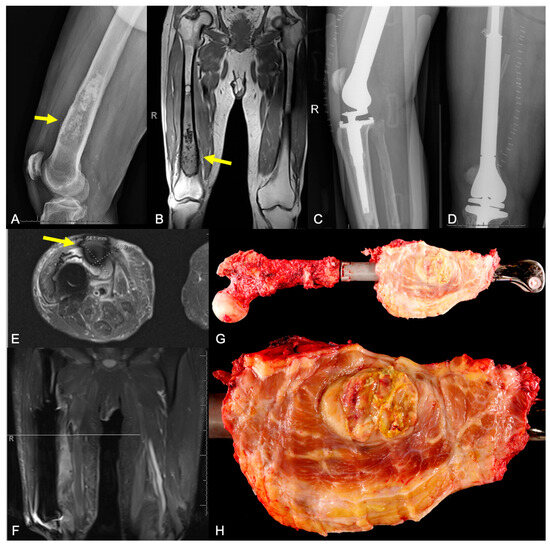

2.3.2. Structural Failure of Allografts